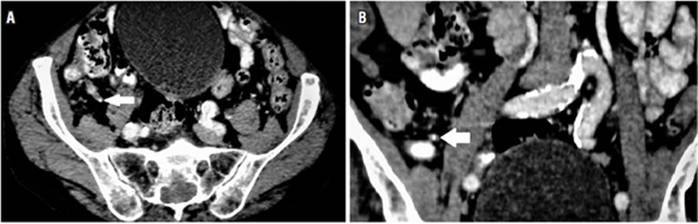

Al sexto día de hospitalización, se realiza una tomografía que reporta apéndice de diámetro normal, sin cambios inflamatorios evidentes, con presencia de fecalito en su interior (Figura 2). Los paraclínicos de control reportan hemoglobina 9,6 g/dL, eritrocitos 3 600 000/mm3, hematocrito 29,8%, leucocitos 5590/mm3 y proteína C reactiva 3 mg/dL. Las especialidades en conjunto examinaron al paciente, quien no evidenció dolor abdominal ni signos de irritación peritoneal, determinaron que el riesgo quirúrgico de este paciente era muy alto y que, al no evidenciarse marcadores de respuesta inflamatoria ni signos de irritación peritoneal, no era candidato para apendicectomía. Decidieron extender el manejo antibiótico con ampicilina/sulbactam hasta 10 días, añadir metronidazol durante 7 días y control con paraclínicos antes del alta.

Cuando la clínica es poco clara, como en el caso reportado, el médico debe apoyarse en los hallazgos paraclínicos e imagenológicos 4,10. La leucocitosis y la neutrofilia en este paciente son poco útiles para el diagnóstico, ya que su infección neumónica, por sí sola, podría dar estos hallazgos 17, por lo que el siguiente paso sería el uso de la tomografía 18), que, en este caso, evidenció la presencia de un apendicolito y confirmó el diagnóstico de apendicitis.